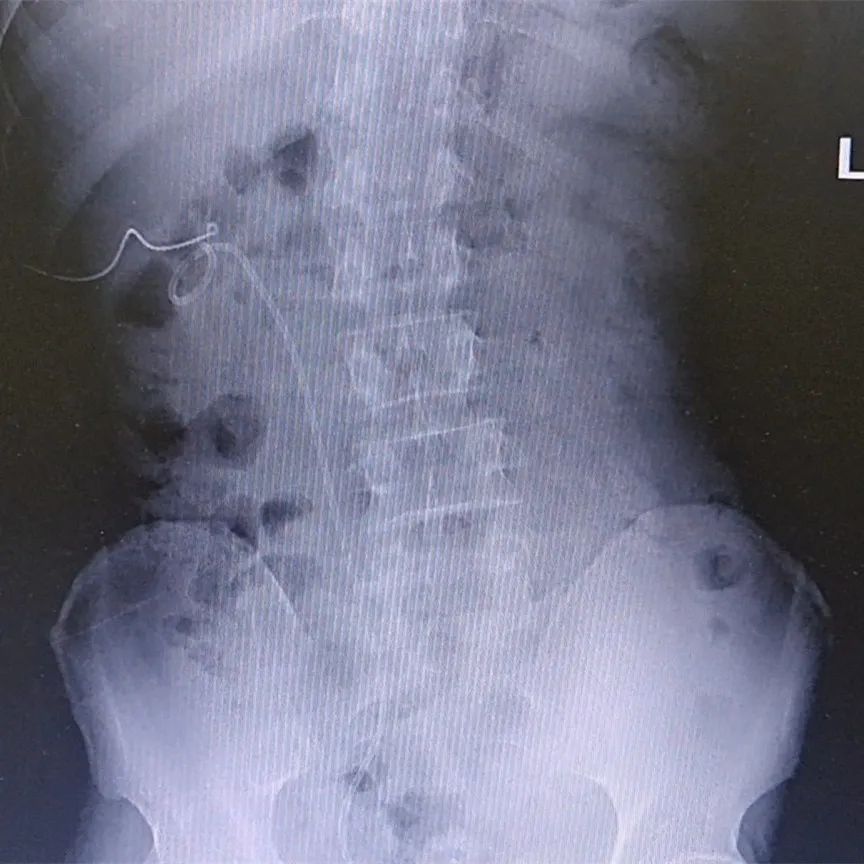

果然,经过X线检查发现王先生又出现了双侧肾结石和右侧输尿管结石,右肾内基本装满结石,考虑到患者结石大、数量多、且肾脏结构呈花瓣状,手术难度会很大,门诊医生不禁犯了愁,有心把患者转到条件更好的三甲医院又怕辜负了患者对我们的信任。庞栋主任带领全科医生慎重讨论后决定让患者入院进行手术治疗。

术前X片显示的结石

术后复查X片

结石已清除干净